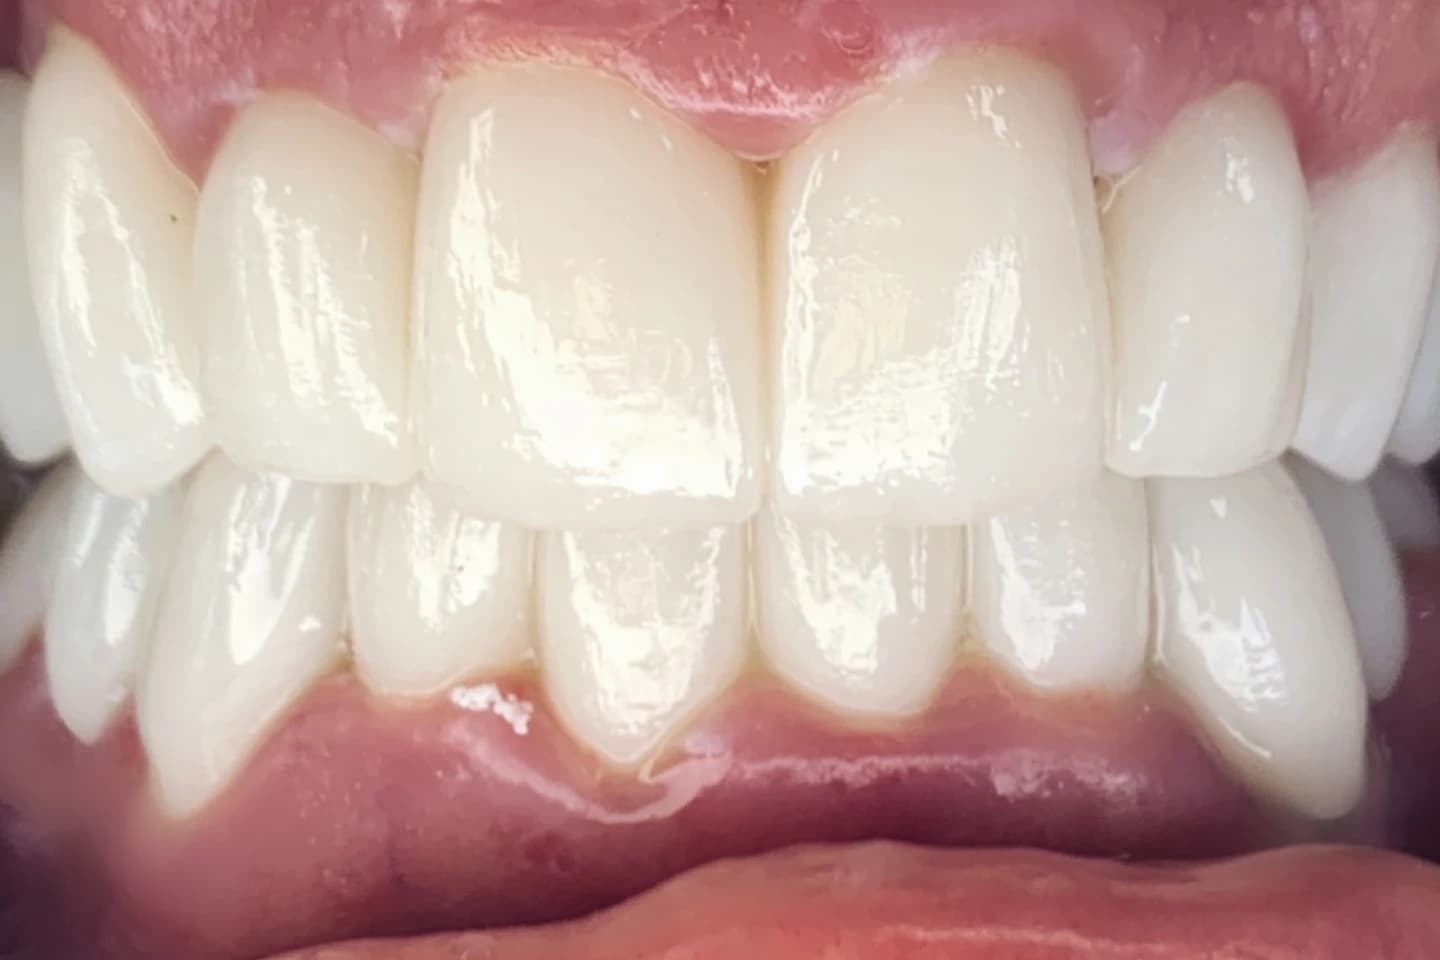

Fasete za zube - pre i posle

- Korigujte manje nepravilnosti i postignite blistav osmeh uz pomoć faseta. Pogledajte kako fasete mogu da transformišu vaš osmeh u samo nekoliko poseta.